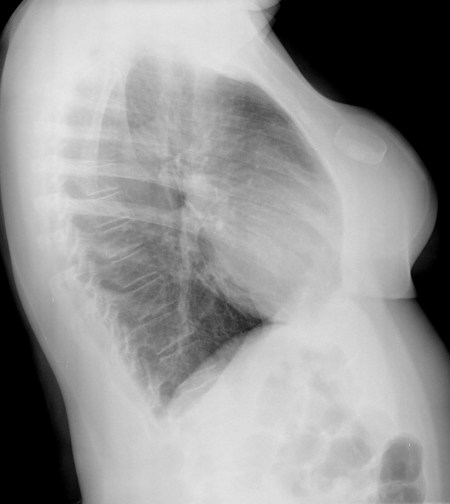

CASO: Febrícula y tos de 4 días de evolución.

Hallazgos:

- En la placa PA se observa una asimetría en los hilios pulmonares, el hilio izquierdo tiene una densidad aumentada.

- Tras examinar la placa lateral se observa un aumento de densidad en la columna que puede ser compatible con una condensación, es el signo de la desnificación vertebral.

SIGNO DE LA DENSIFICACIÓN VERTEBRAL: En la radiografía lateral normal, la densidad de la columna torácica tiende a disminuir desde la parte superior hasta el diafragma; la alteración de ese patrón por la presencia de una densidad superpuesta a la columna, indica la existencia de una consolidación pulmonar. Este signo adquiere especial valor cuando en la proyección posteroanterior la consolidación está oculta en el espacio retrocardíaco o en la base pulmonar.